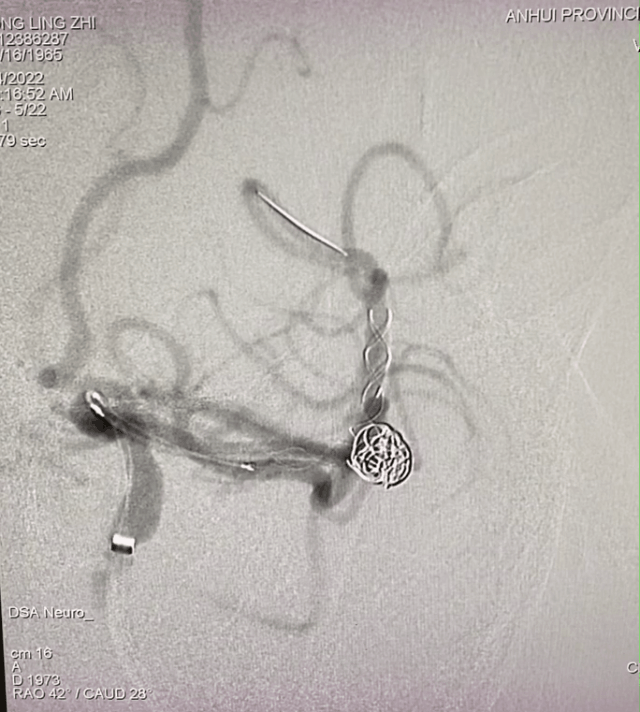

脑血管造影

左侧大脑中分叉处(上干)动脉瘤,夹层可能性大;瘤体4.3mm×5.1mm,瘤颈5.8mm。

远近端载瘤动脉直径分别为2.17mm、2.58mm。